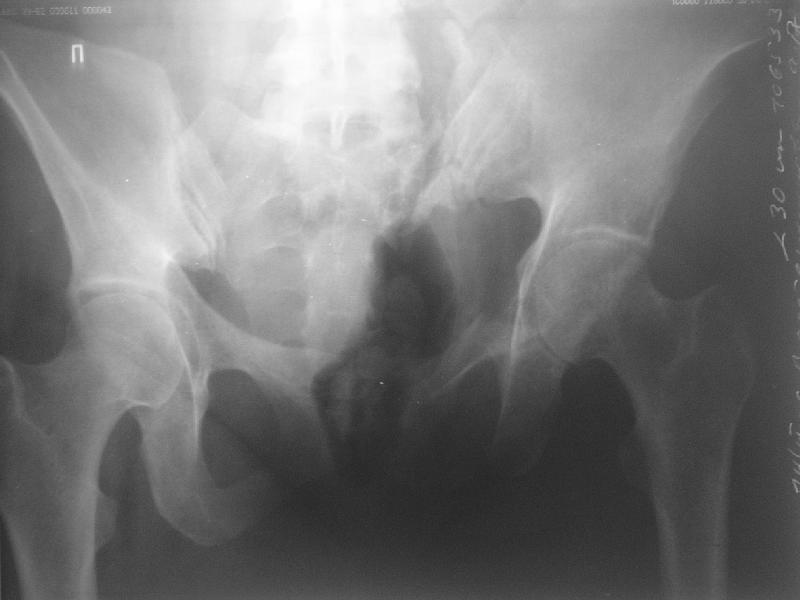

Прооперировали молодую девушку 32 лет спустя 9 мес после травмы. Имелся стойкий болевой синдром, неопороспособность левой н/конечности, моторные и сенсорные нарушения в левой голени и стопе, патологическая подвижность левой половины таза. Первым этапом закрыто в аппарате исправили деформацию ( в течении 2,5 нед). Вторым закрытое введение илиосакральных винтов в крестец (канюллированные 7,2 мм Chm) + туннелизация зоны псевдоартроза спицама Киршнера, реконструкция передних отделов таза, накостный остеосинтез . Аппарат частично демонтирпован, оставлена "передняя рама" После устранения деформации отмечен регресс неврологической симптоматики, уменьшение болевого синдрома. Интересующие вопросы: 1. Прогноз для сращения псевдоартроза крестца. 2. сроки нагрузки весом левой половины таза. Буду очень признателен за ваши мнения по этому поводу.A female 32 y.o. admitted to our unit 9 months after initial injury with pain, inability to bear weight at the left lower limb, sensor and motor disturbances in the left foot and tibia, with mobility of the left hemipelvis.At first closed reduction was performed by an external fixator within 2,5 weeks. After correction her pain decreased and some neurological progress was achieved. Now two iliosacral screws 7,2 mm were inserted, and anterior lesion was fixed by a plate. External fixator was partially unmounted, only anterior frame left in place.Images attached.How would you evaluate chances of healing of the sacrum with the current position?When would you allow weight-bearing of the left leg?THX in advance.